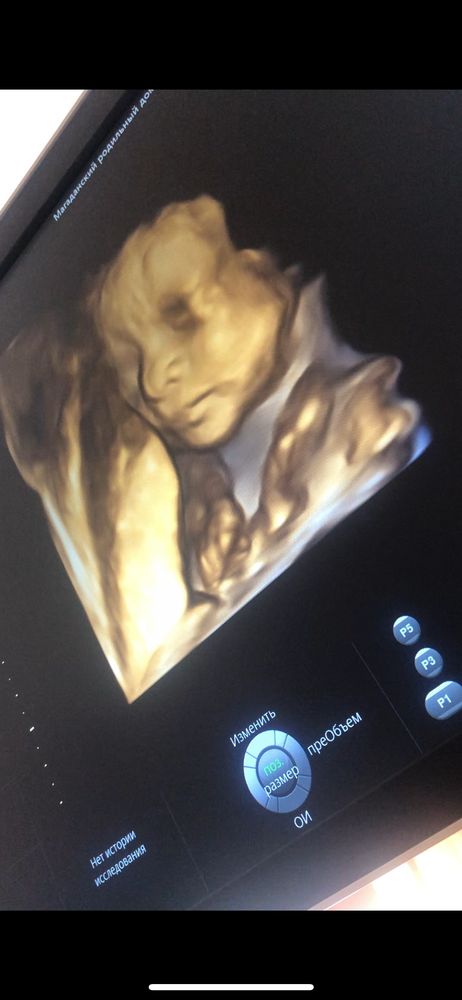

судя по 3д узи - наш мальчик копия папа😻